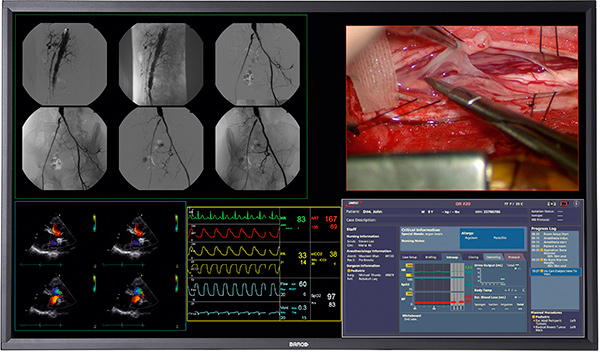

Barco is launching its new 58″ 4K surgical display, helping to bring the high-resolution video standard to top-end operating suites everywhere. The MDSC-8258 is a full color screen and will display DICOM-compliant color and grayscale images at 700 cd/m² brightness and 4000:1 contrast ratio, making it practical for simultaneous display of live fluoroscopy, pre-operative images, and live video such as from an endoscope.

The resolution of 4K monitors is typically 3840 x 2160, which is about four times the number of pixels of 1080p displays. To handle so much data, the monitor requires a dual DVI input, which it has two sets of for using different video sources.